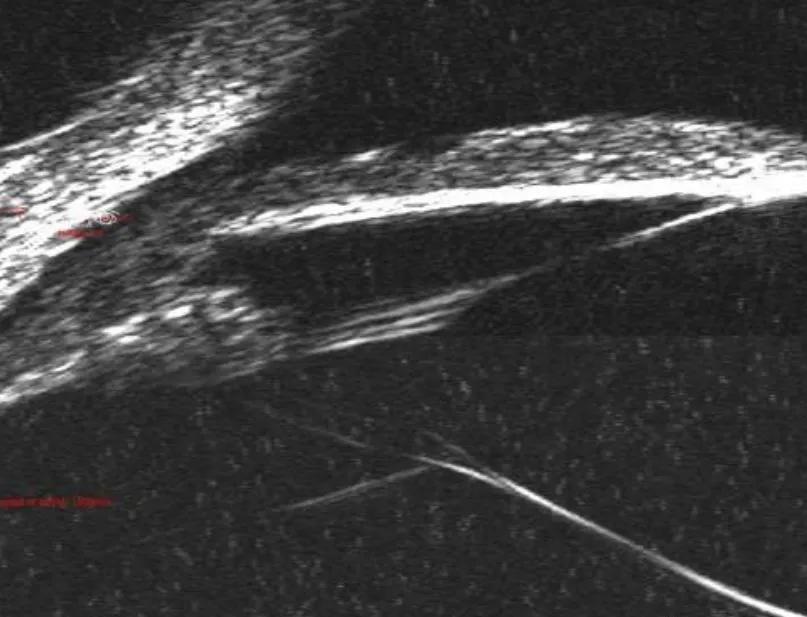

(2)囊袋大小,可根据晶体直径(UBM);